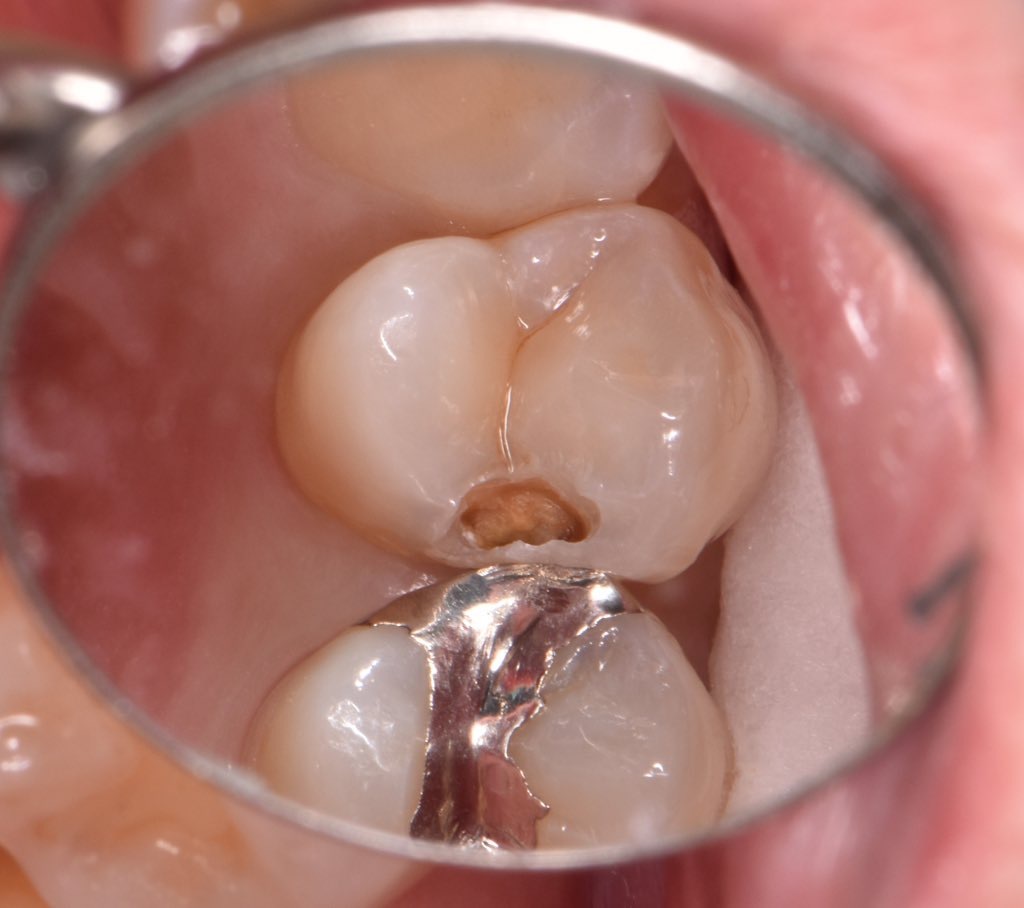

銀歯の二次虫歯をレジン(保険治療)で修復 治療症例集

左側6番シーラント下のカリエス|西宮市の西宮北口駅の歯医者|にし

症例】検診で見つかった金属の詰め物の下の虫歯の治療|渋谷の歯医者